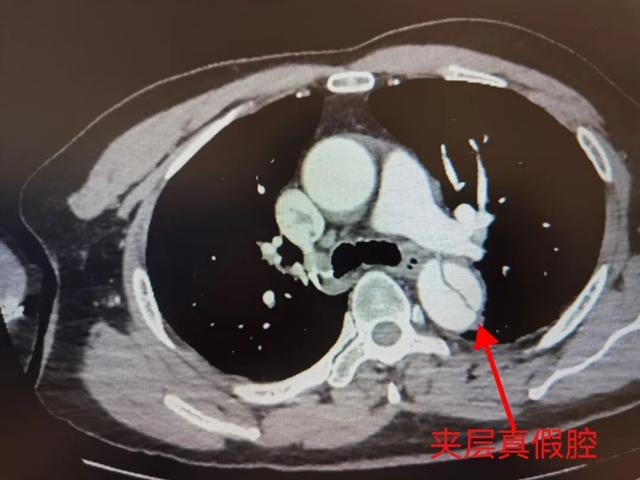

证实为胸腹主动脉夹层

双肾动脉夹层

右侧髂总动脉夹层

主动脉夹层是一种紧急的血管疾病,通常发生在主动脉壁的内膜和中膜之间形成的裂缝处。这种裂缝会导致血液穿过夹层,形成一个假性的血管腔,增加了主动脉壁的压力和脆弱性。

主动脉夹层的诊断通常通过临床症状、体格检查和影像学检查来确认。其中,血管CTA扫描是最常用的检查方法,可以直观地显示主动脉夹层的位置和程度。